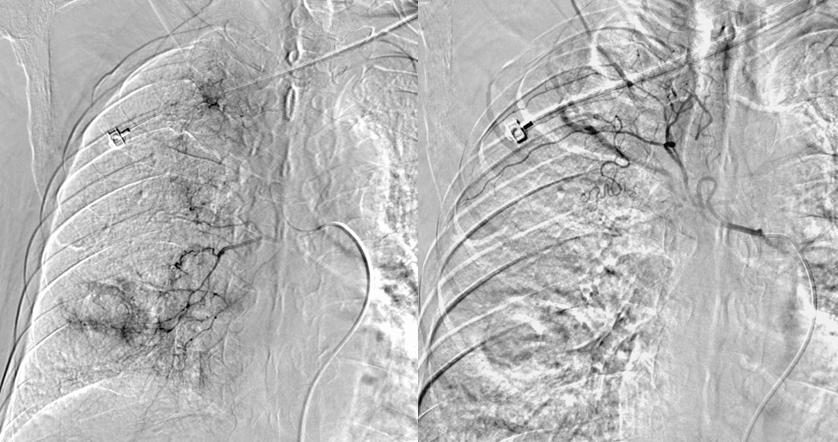

介入手术治疗(2020.7.31)

*支气管动脉造影:右侧支气管动脉与右侧最上肋间动脉共干。

*支气管动脉造影:右下肺癌性空洞壁形成。

*栓塞治疗:奥沙利铂100mg灌注化疗后300-500μm微球1瓶搭载吉西他滨1000mg进行适量栓塞, 栓塞后复查肿瘤染色大部分消失。